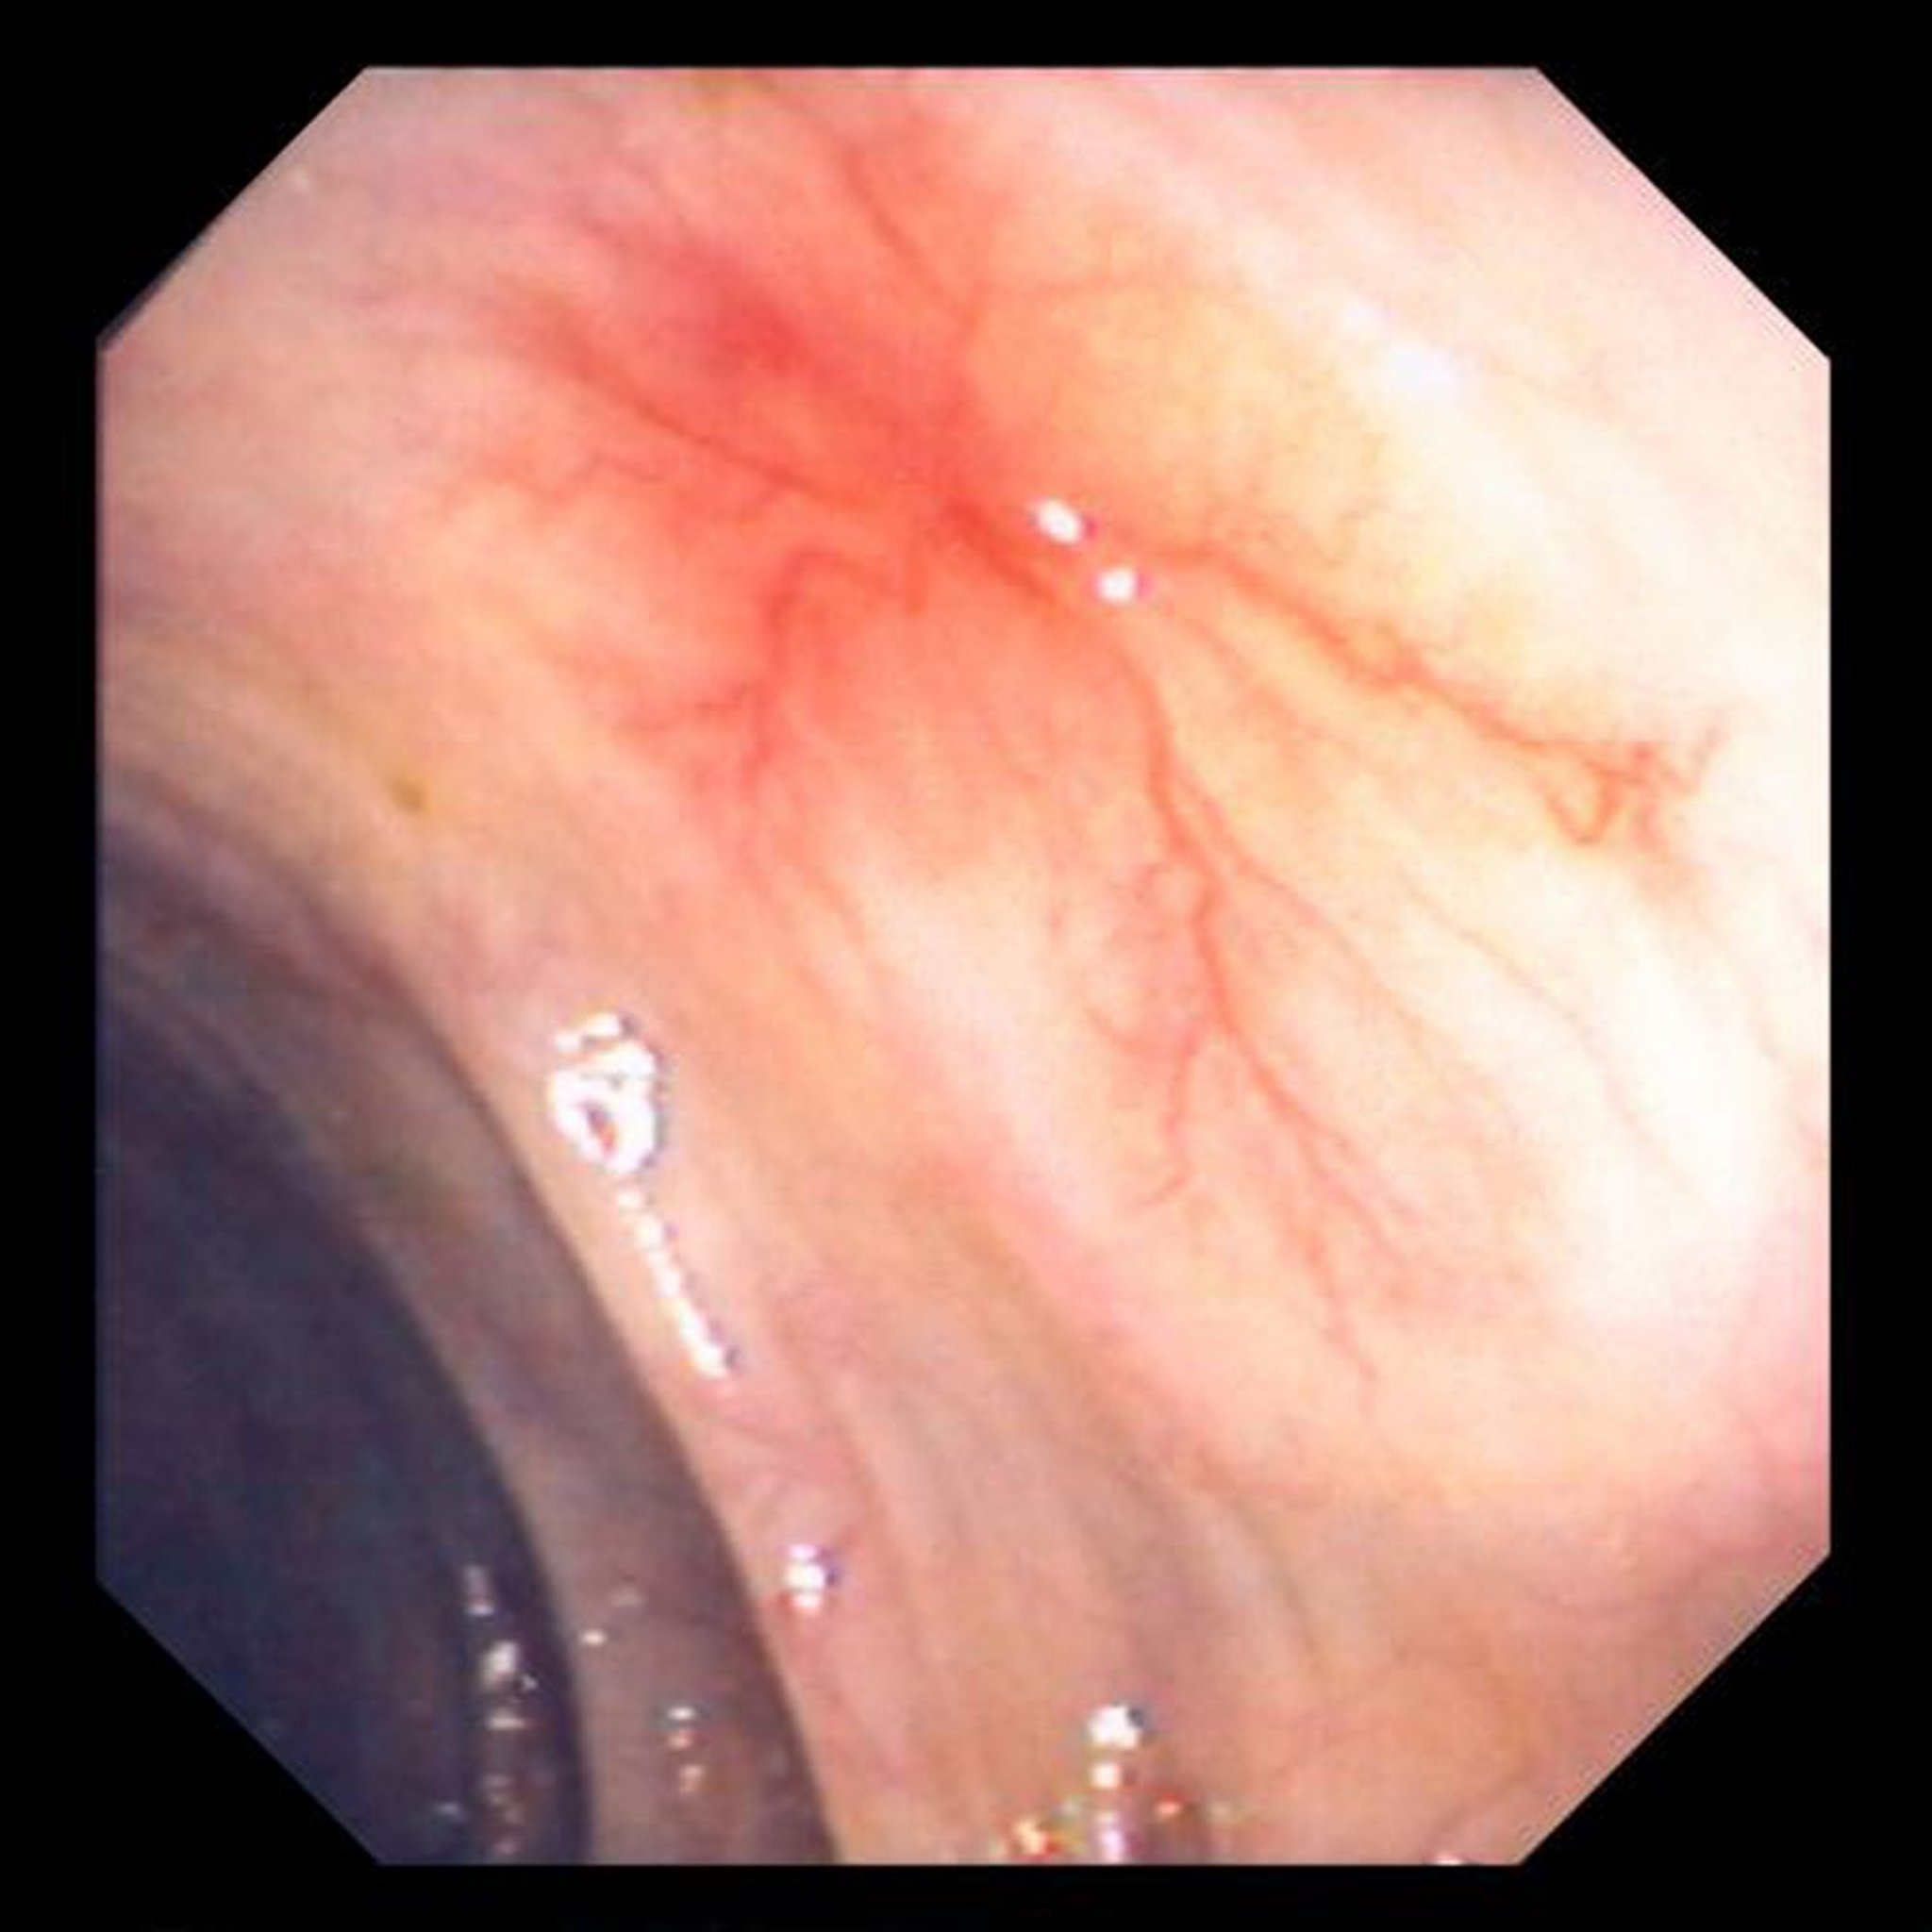

Angiodisplasia

Esta foto mostra ectasia vascular na parede do intestino.

Image provided by David M. Martin, MD.

Lesões vasculares gastrointestinais